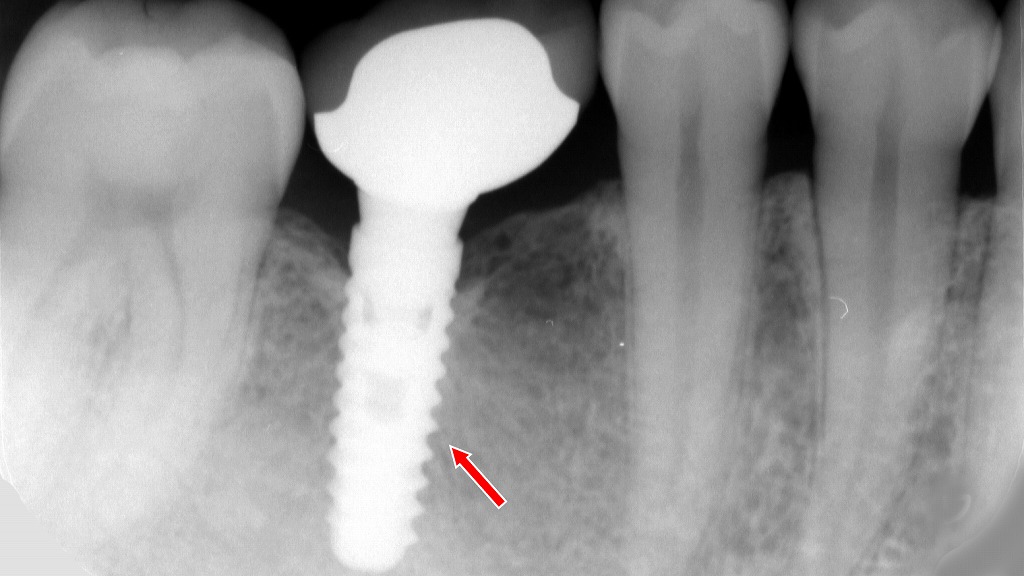

歯根破折後の治療選択:下顎6番部に行ったインプラント治療の術中・術後X線所見

歯根破折により保存が不可能となった下顎6番を抜歯後、インプラント治療で機能回復を図った症例。術中写真では適切な位置・深度にフィクスチャーが埋入されている様子が確認でき、X線画像では骨結合の獲得後に最終補綴装置が装着され、咬合支持が安定していることが示されている。外科処置から補綴まで一連の治療ステップにより、長期的な咀嚼機能の回復が期待される。